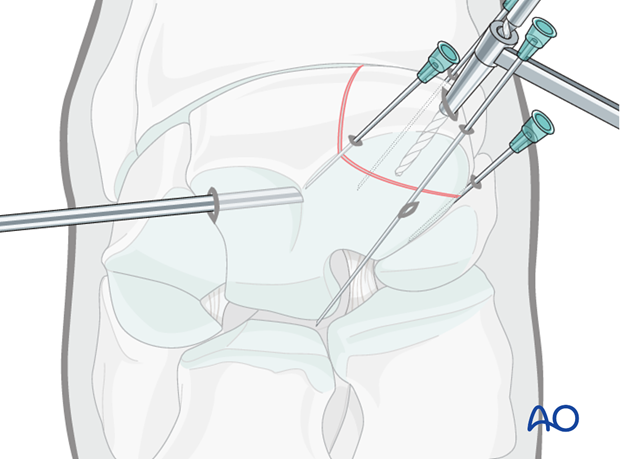

The proximal medial and lateral margins of the fracture are defined by arthroscopically guided percutaneous insertion of hypodermic needles.

It is important that these needles are placed perpendicular to the dorsal surface of the carpus to accurately delineate the fracture width.

An 18 gauge spinal needle is subsequently placed midway between these two needles close and parallel to the proximal articular surface and directed across the midpoint of the fracture as close to 90 degrees as possible. This needle is the most important directional guide for implant placement.

The configuration of most frontal plane slab fractures of the radial facet are such that the tip of the needle usually lodges in the palmar fossa of the bone and can be implanted in the non-articular surface to stabilize the spinal needle sufficiently.

Once the spinal needle has been placed, a further 18 gauge needle is inserted parallel to it into the carpometacarpal joint.